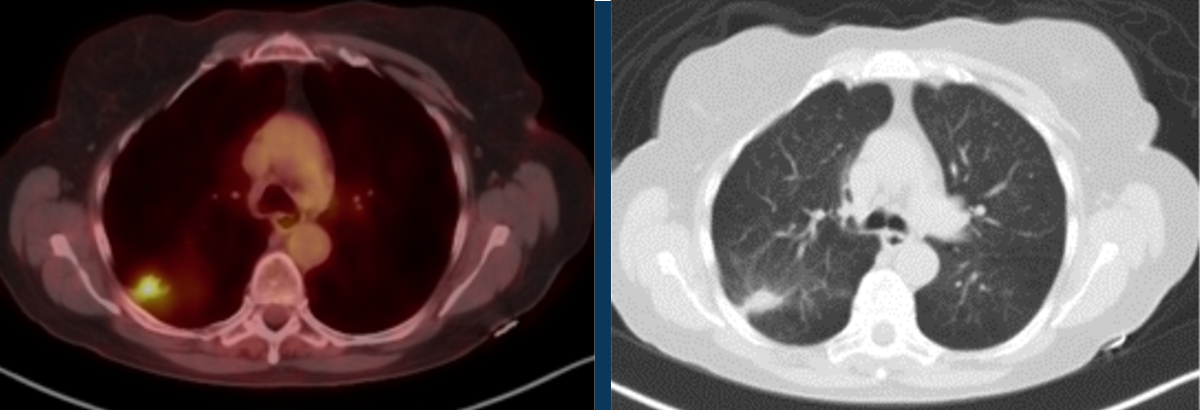

2018 study – Below threshold SUV. SUV max 2.2

2020 study – Biopsy-proven adenocarcinoma. SUV max 5.4